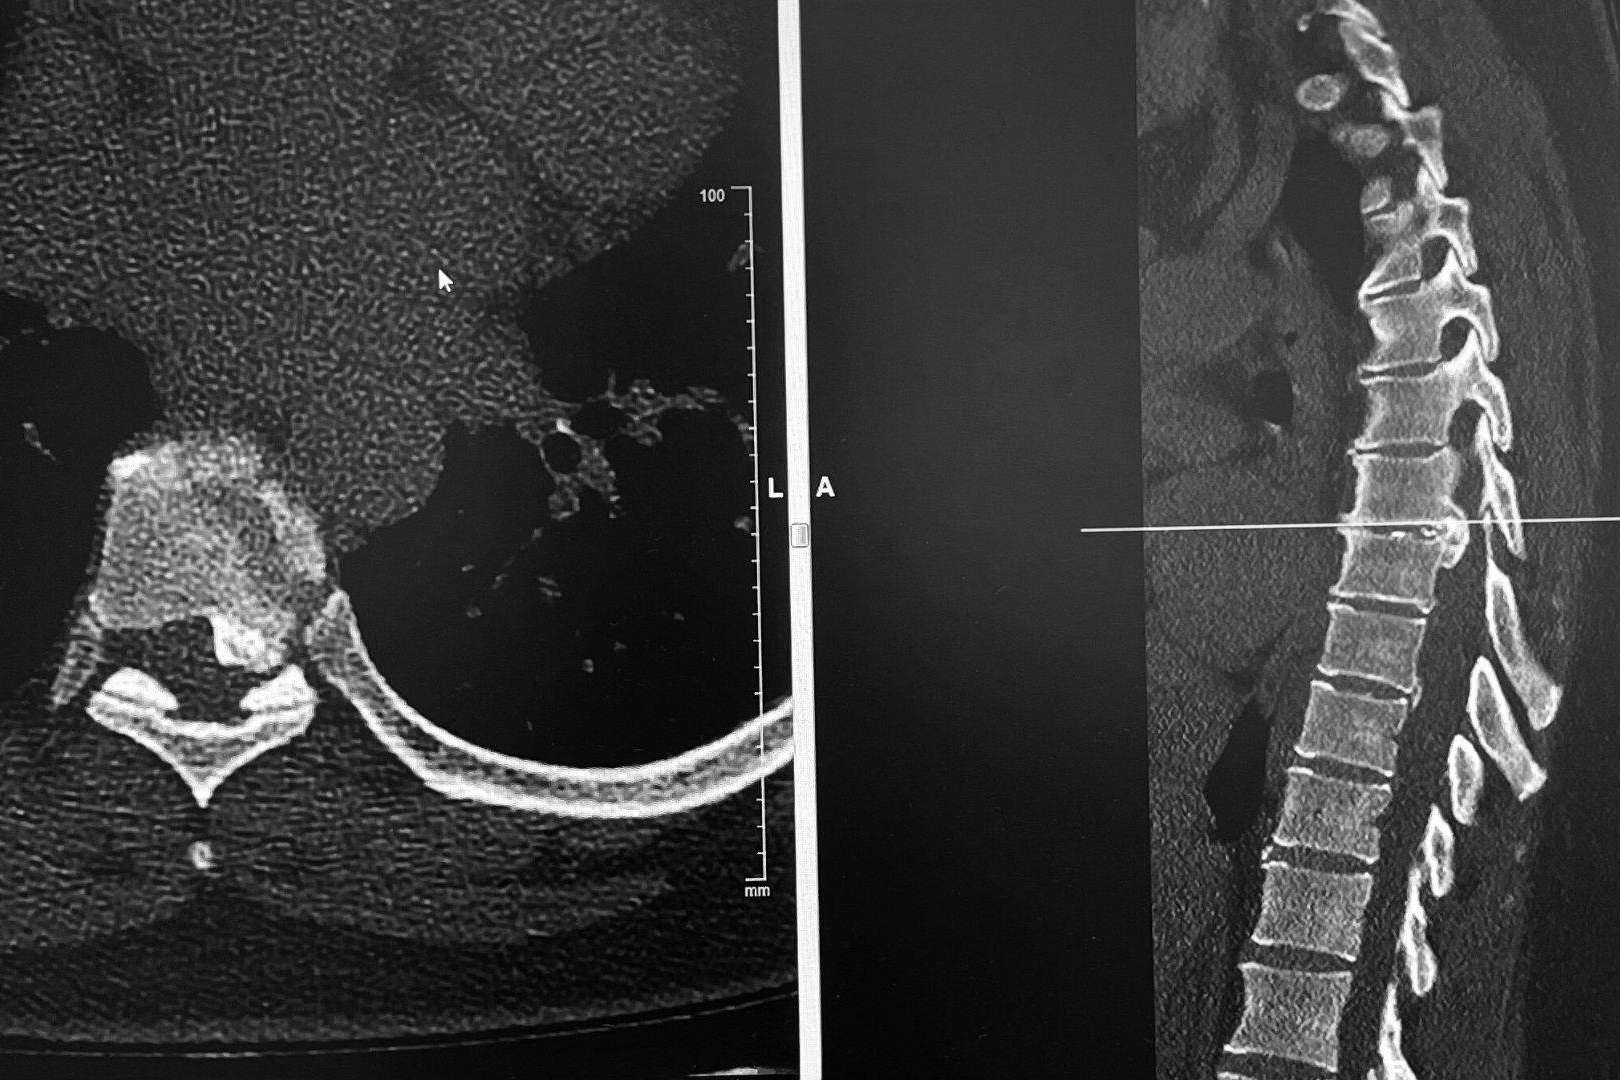

Los discos dorsales son tejidos semejantes a un cojín esponjoso que se encuentran entre las vértebras de la columna. Las hernias aparecen cuando uno de los discos sobresale de entre las vértebras, presionando los nervios y la médula, lo que produce dolor y otros síntomas como la sensación de hormigueo, dependiendo del lugar en el que se originen.

Es común que con la edad, el material gelatinoso que amortigua los discos se debilite y desaparezca, posibilitando movimientos que los desvíe de su posición original, produciendo de esta manera una hernia. Cuando el disco llega a presionar la médula o algún otro nervio importante, es posible que el paciente presente sensación de adormecimiento en las extremidades y, en casos más graves, debilidad en las extremidades o dificultad para el movimiento.